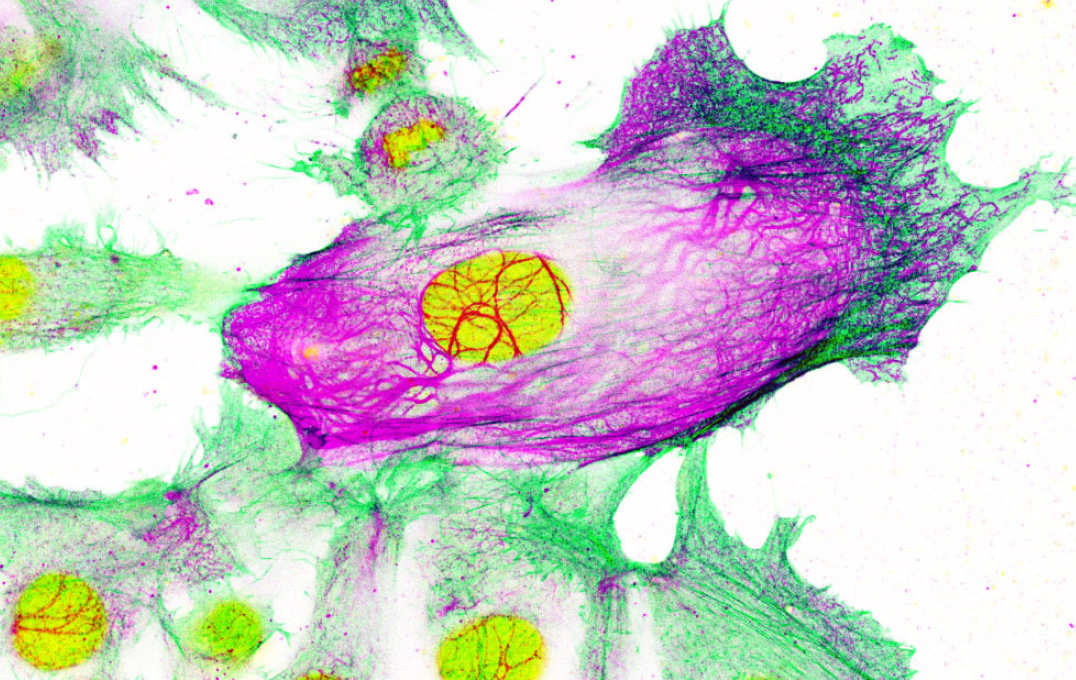

• Drug-resistant breast cancer cells surrounded by non-resistant cells. The cell nucleus is shown in yellow, while the cell’s ‘scaffolding’ is shown in green and purple. Keratin-80 is shown in purple.

Drug-resistant breast cancer cells surrounded by non-resistant cells. The cell nucleus is shown in yellow, while the cell’s ‘scaffolding’ is shown in green and purple. Keratin-80 is shown in purple.